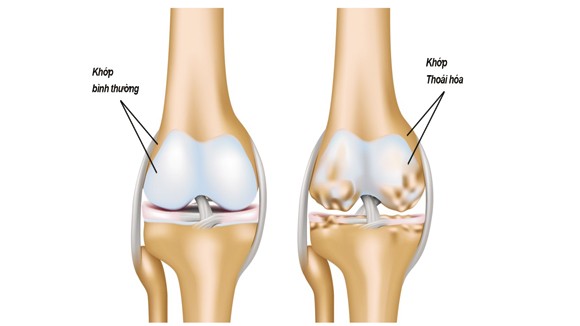

Thoái hóa khớp là gì?

Thoái hóa khớp là sự hao mòn, hư tổn của sụn khớp, dịch khớp cũng như các thành phần kế cận như vùng bao khớp, vùng xương tiếp giáp... Khi sụn khớp bị thoái hóa, lớp sụn dần mất đi, dịch khớp dần cạn kiệt khiến cho các đầu xương tiếp xúc trực tiếp với nhau ở các vị trí khớp gây nên tình trạng đau nhức tê buốt, đặc biệt khi phải vận động như mang vác đồ vật, lên xuống cầu thang, thay đổi tư thế. Bệnh không mang tính cấp mà diễn tiến theo tuổi tác, thời gian, thường xuất hiện sau tuổi 30, tăng dần và phổ biến ở tuổi trung niên.

Các biểu hiện ban đầu thường gặp đó là đau nhức khi mang vật nặng hoặc vận động với mức độ cao. Nặng hơn là sưng, nóng đỏ xuất hiện ở các khớp chân, tay, háng, cột sống, đốt sống cổ, bả vai... Với những bệnh nhân dịch khớp suy giảm, các khớp thường bị khô khiến cho việc vận động gặp nhiều khó khăn, thậm chí khi cử động còn nghe thấy tiếng lạo xạo, răng rắc ở các khớp.

Nếu không có những giải pháp chữa trị kịp thời sẽ dẫn đến sưng khớp, viêm khớp rồi gai khớp, cứng khớp, người bệnh sẽ rất khó vận động ngay cả những hoạt động sinh hoạt thường ngày.